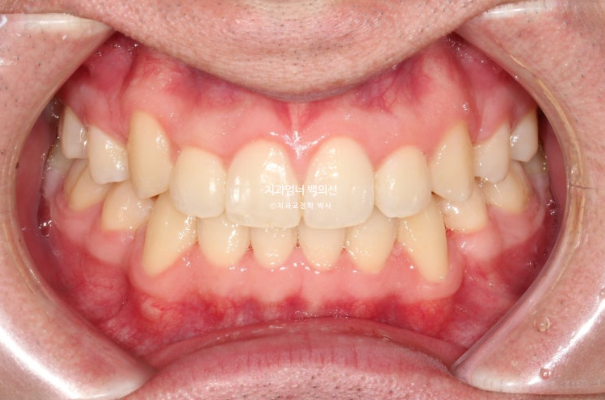

24년 12월부터 25년 4월까지 4개월간 두 번째 추가장치를 다 낀 후 치료를 종료하였습니다.

25.04

교정치료의 기본은 물샐틈 없는 이븐한 교합입니다.

교합이 좋지 않으면 교정치료를 마무리 짓지 않습니다.

이제 전 후 비교 보겠습니다.

22.09~25.04

재제작은 총 2회 하였으며 치료기간은 2년 6개월 입니다. 중간중간 장치제작기간을 제외하면 실제 치료기간은 2년 2개월 입니다.